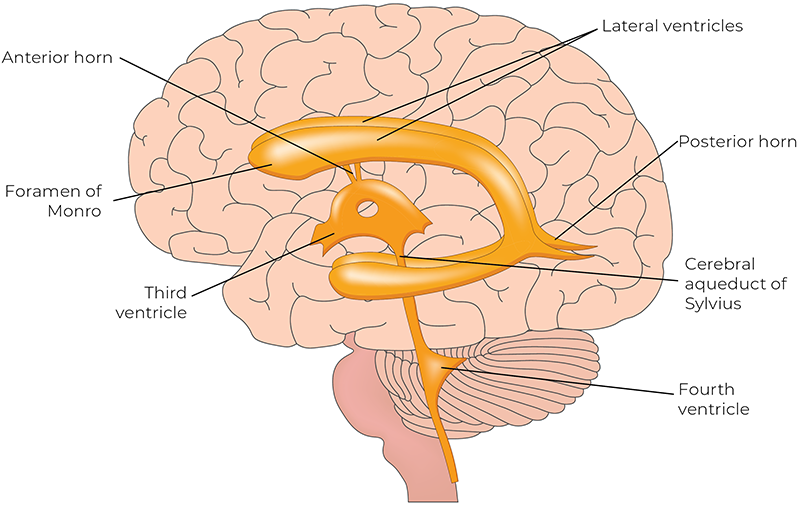

In the 1970s, Dr. John E. Upledger, an osteopathic physician, observed a slow rhythmic motion of the spinal dura mater (the outer membrane surrounding the spinal cord) during a neck surgery. The observed movement of the dura mater was reported to be independent of breathing and heartbeat. This direct surgical observation inspired him to investigate what he called the “craniosacral rhythm.”

The pacemaker for the circadian rhythm is in the hypothalamus, near the third ventricle of the brain. This pacemaker generates an internal representation of solar time that is conveyed to every cell in the body, coordinating the daily cycles of physiology and behavior. Today, there is growing recognition that chronic disruption of circadian rhythms has profound effects on our health. Is there a link between what we’re learning about the pacemaker of the circadian rhythm and CSR?

The Pacemaker Theory positions the CSR as one of several neurogenic rhythms—autonomously generated patterns of electrical activity produced by networks of oscillating neurons located in the brain stem near the fourth ventricle.11 These neurons act as central pacemakers, producing rhythmic discharges independent of respiration or cardiac rhythms. The autonomic nervous system integrates multiple physiological systems and serves as a critical conduit for communication between a central pacemaker in the brain stem and peripheral oscillators in vascular structures.

Peripheral oscillators in smooth muscle and endothelial tissues contribute to vasomotion—the rhythmic contraction and relaxation of blood vessels.12 When vasomotion is regulated by neural impulses rather than local metabolic factors, it is called neurogenic vasomotion. This centrally driven vasomotion is believed to be modulated by a brain stem pacemaker that communicates descending regulatory signals primarily via sympathetic spinal tracts.

The central autonomic network—a coordinated system of cortical, subcortical, and brain stem structures—acts as the integrative hub linking the pacemaker with wider physiological systems to maintain homeostasis.13 Within this framework, the CSR is understood as a system-wide oscillatory rhythm generated at approximately 6 cpm.14 It is transmitted throughout the body via neurogenic vasomotion, resulting in oscillations in blood vessel diameter, tissue pressure, and fluid flow. These oscillations are not confined to any specific region; rather, they can be palpated throughout the body by skilled practitioners. Ultimately, the Pacemaker Theory provides a scientifically plausible, biologically grounded framework for understanding the CSR as a legitimate neurophysiological rhythm.